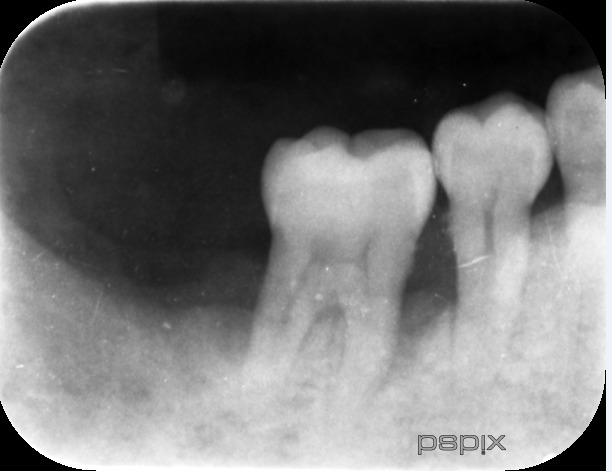

40代女性

右下6番の歯周病です。

今にも抜けそうな状態でしたが